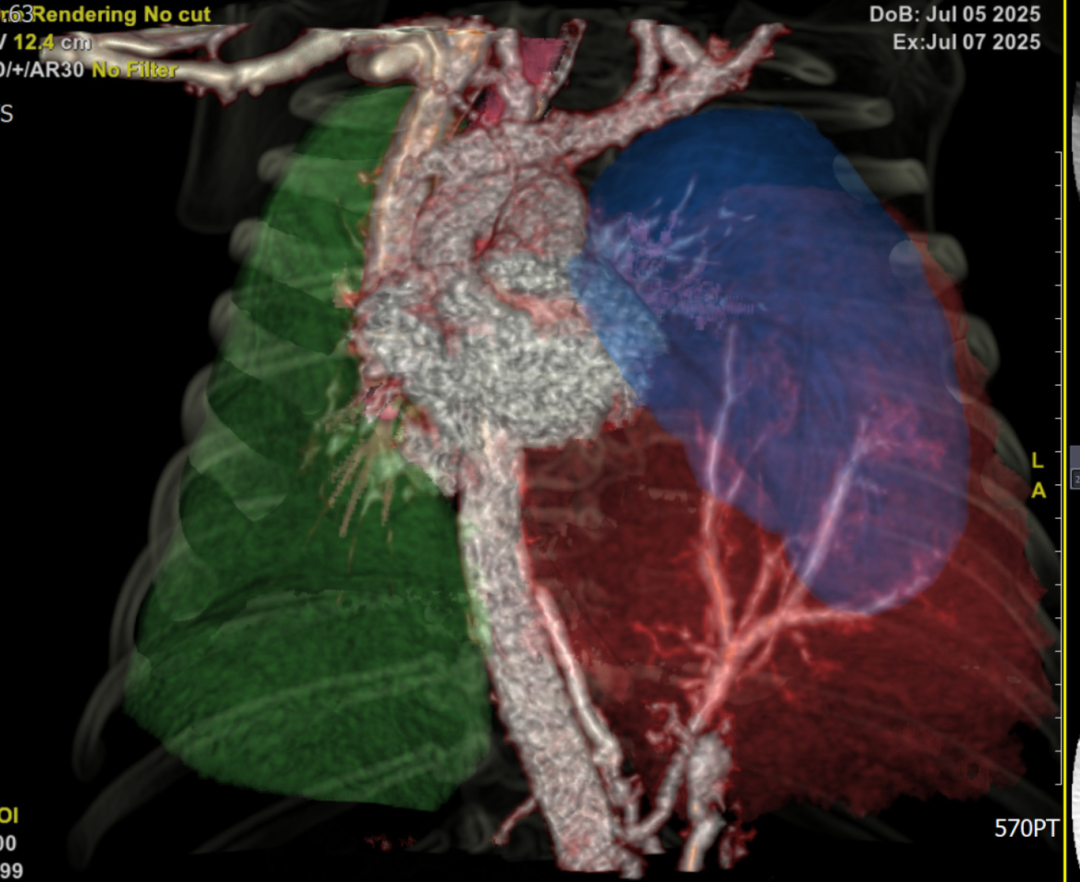

新生儿科团队则需关注患儿出生后呼吸支持方案,提前备好呼吸机和 CPAP 设备。放射科陈凤英主任医师通过三维重建技术,清晰标注出肿块与心脏、大血管的位置关系,为手术规划提供 "导航图"。

长期以来,我院小儿外科积累了丰富的胎儿及新生儿手术经验,麻醉科对此类患儿的术中监护也经验十足,但面对患儿胸腔空间狭小,肿块紧邻心脏和大血管,稍有不慎就会引发致命出血等因素,外科副主任唐华建还是强调了手术挑战性:这台手术如同 "在刀尖上跳舞"—— 整个手术过程肿块都随着心脏跳动而摆动,既要完整切除肿块,又要精准结扎异常血管,还要避免损伤正常肺组织。

手术在胸腔镜下进行,3个0.5 cm的切口成为 "战场入口"。在高清内镜视野下,唐华建精准定位直径仅约3 毫米的异常供血血管,使用特制的微型钳夹成功结扎。分离肿块时,他像 "剥洋葱" 般逐层剥离粘连组织,动作轻、准、稳。

1小时 20 分钟后,长达6cm的肿块被完整切除,术中出血量控制至仅2ml。术后病理报告证实为"隔离肺"。